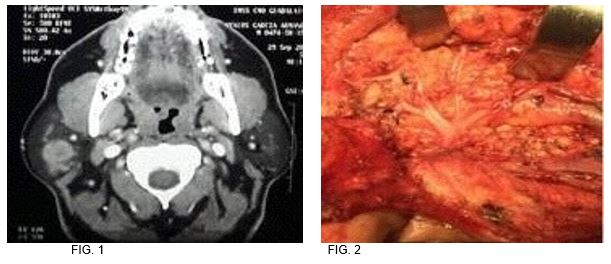

Caso 1: Masculino 49 años de edad, antecedente de tabaquismo e hipertensión, tumor parotídeo derecho de 5x3.5x2.5 pétrea. fue sometido a parotidectomía supraneural, resultando en melanoma maligno nodular con patrón sarcomatoide. (FIG. 1-2)

1

2